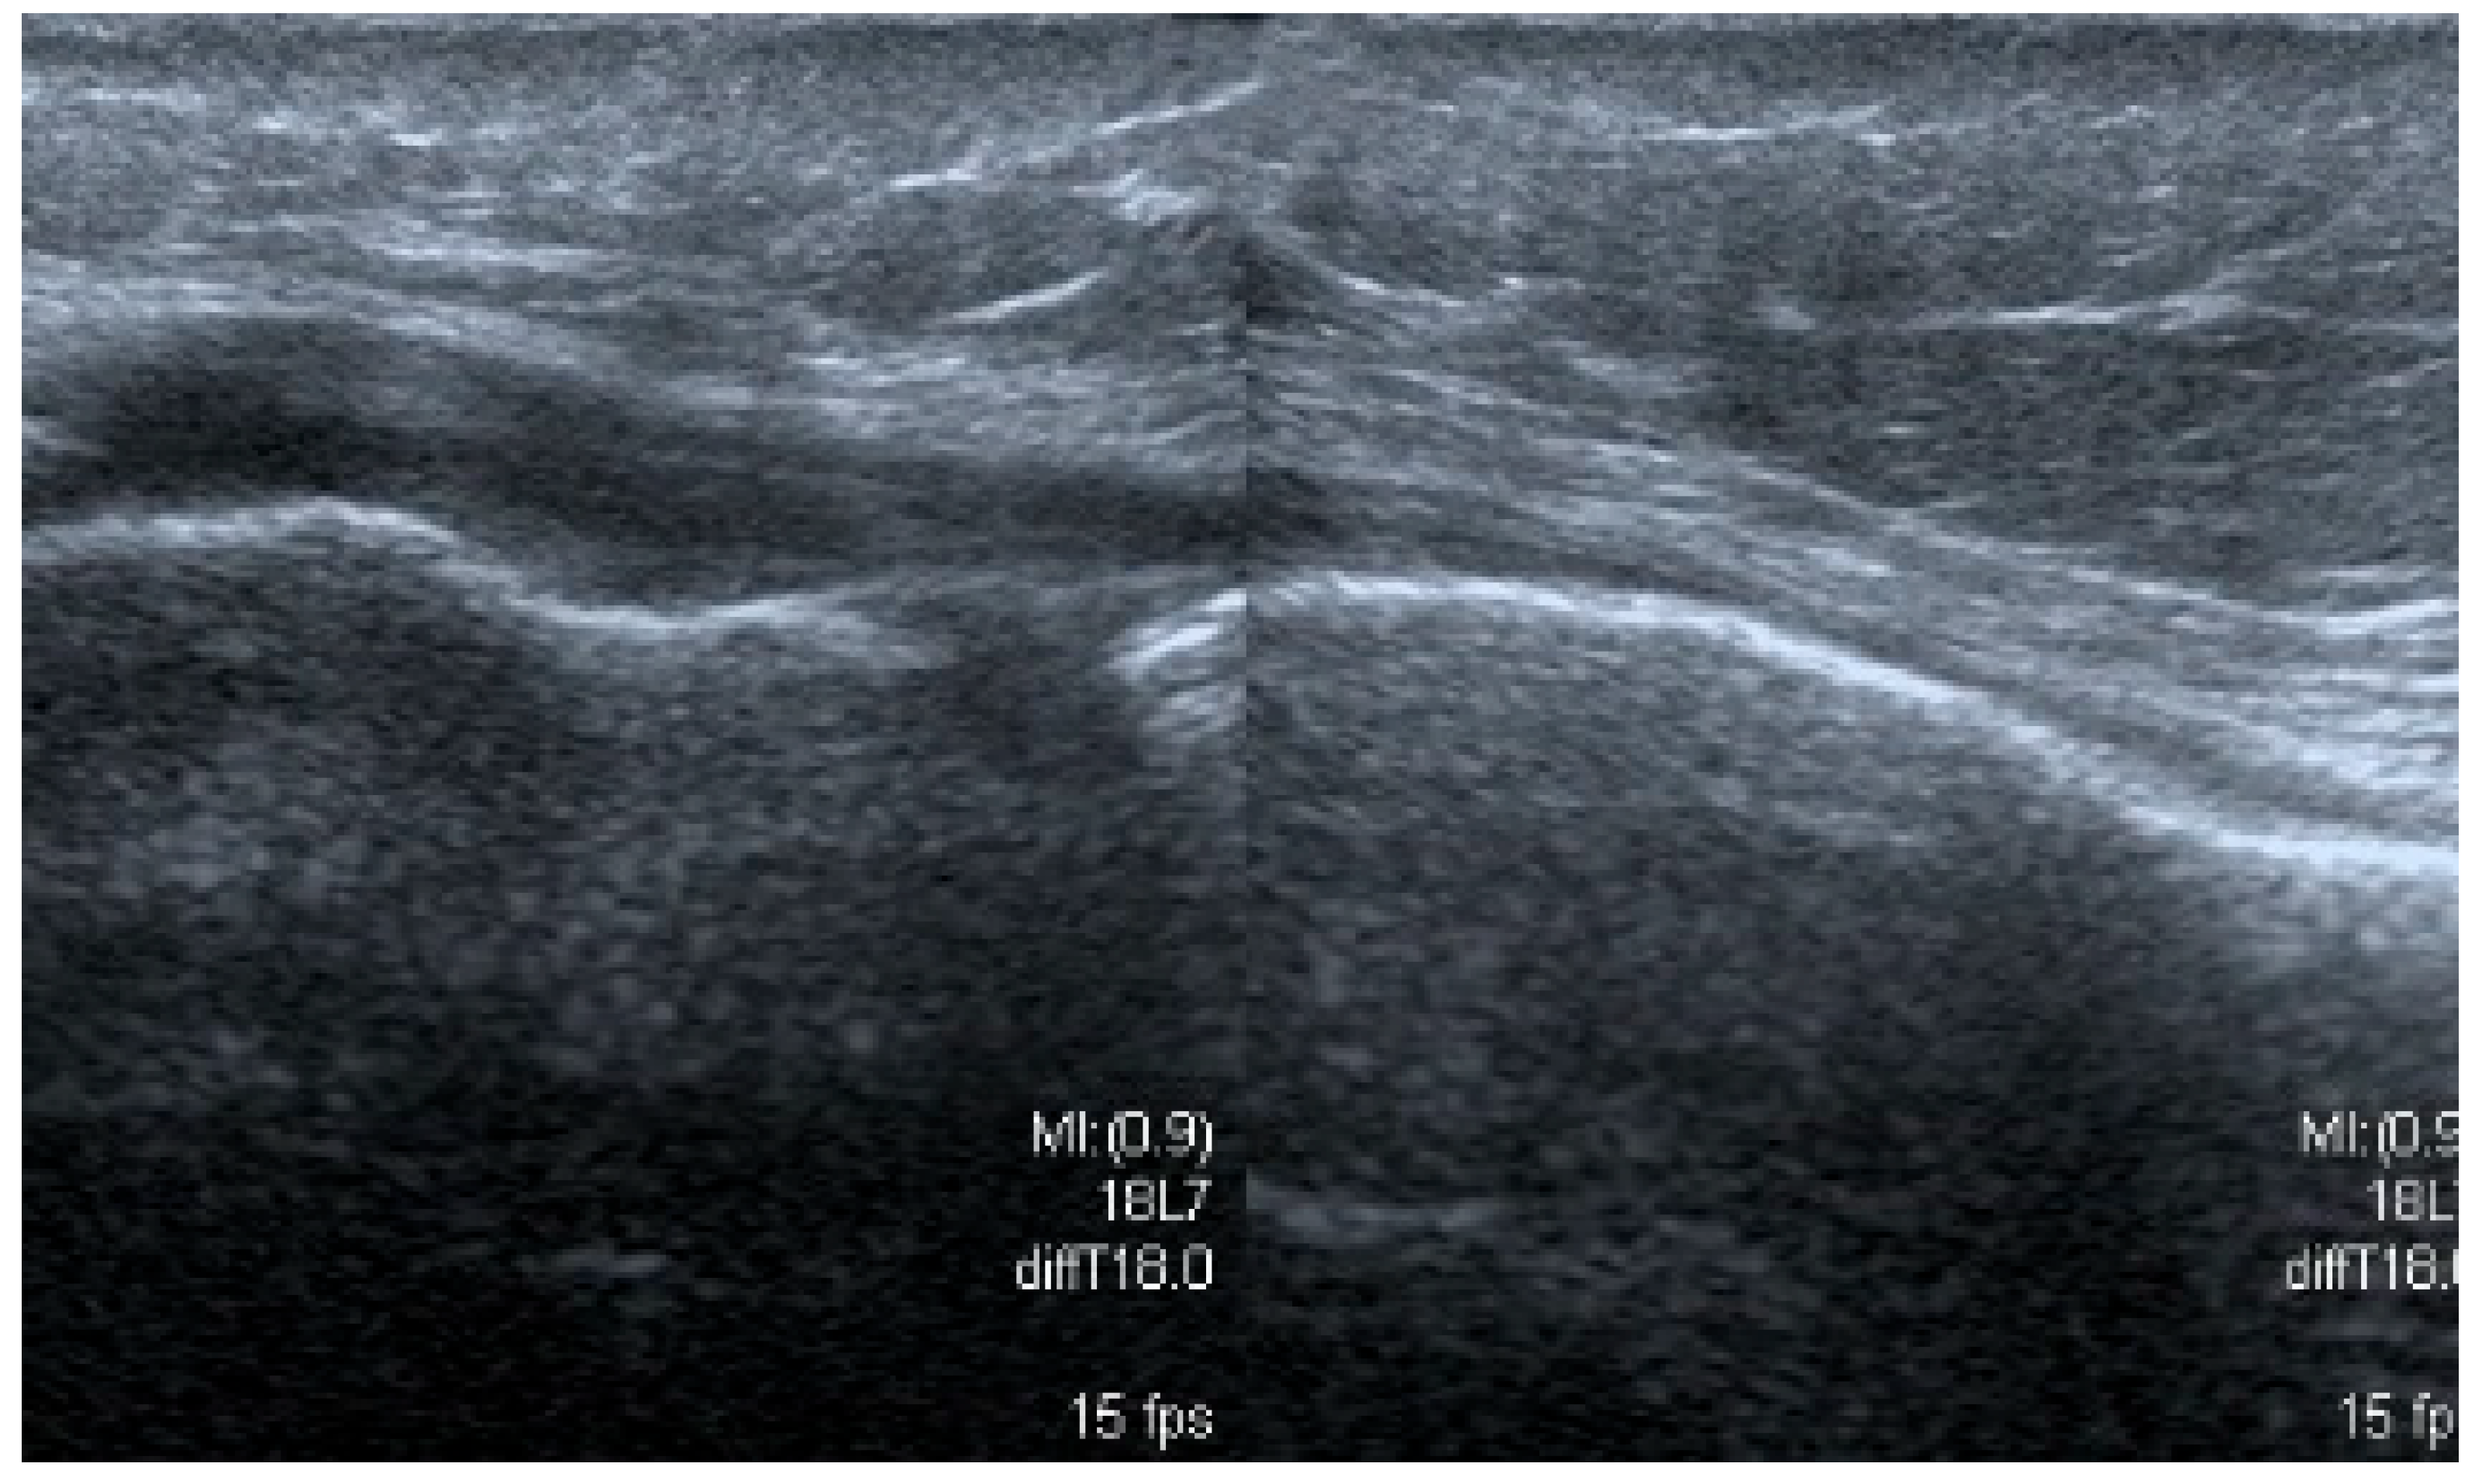

3.1.5. Degenerative Changes of Menisci

3.2. The Results of the Retrospective Analysis